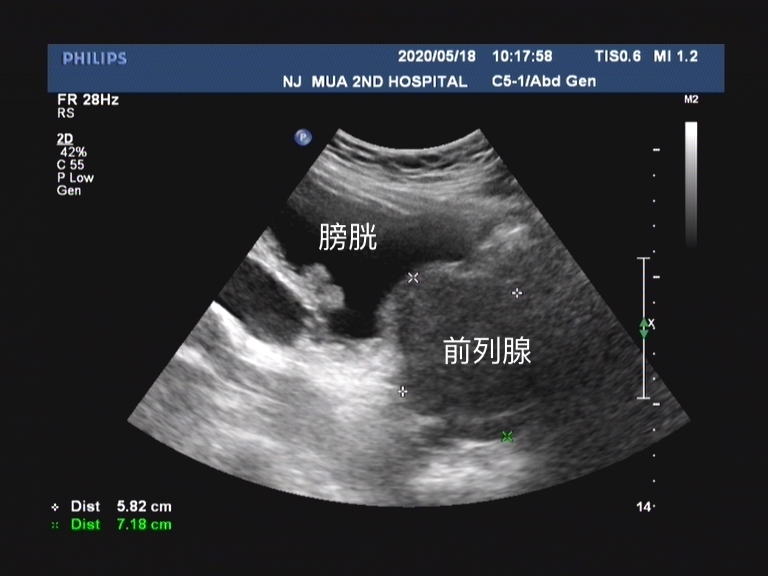

研究内容是肾宝片对于肾阳亏虚型前列腺增生的疗效,主要的观察指标是使用药物后第4周、第8周及第12周时候中 医证候疗效、中医证候单项评分、国际前列腺症状评分(IPSS)总分及生活质量评分变化情况。